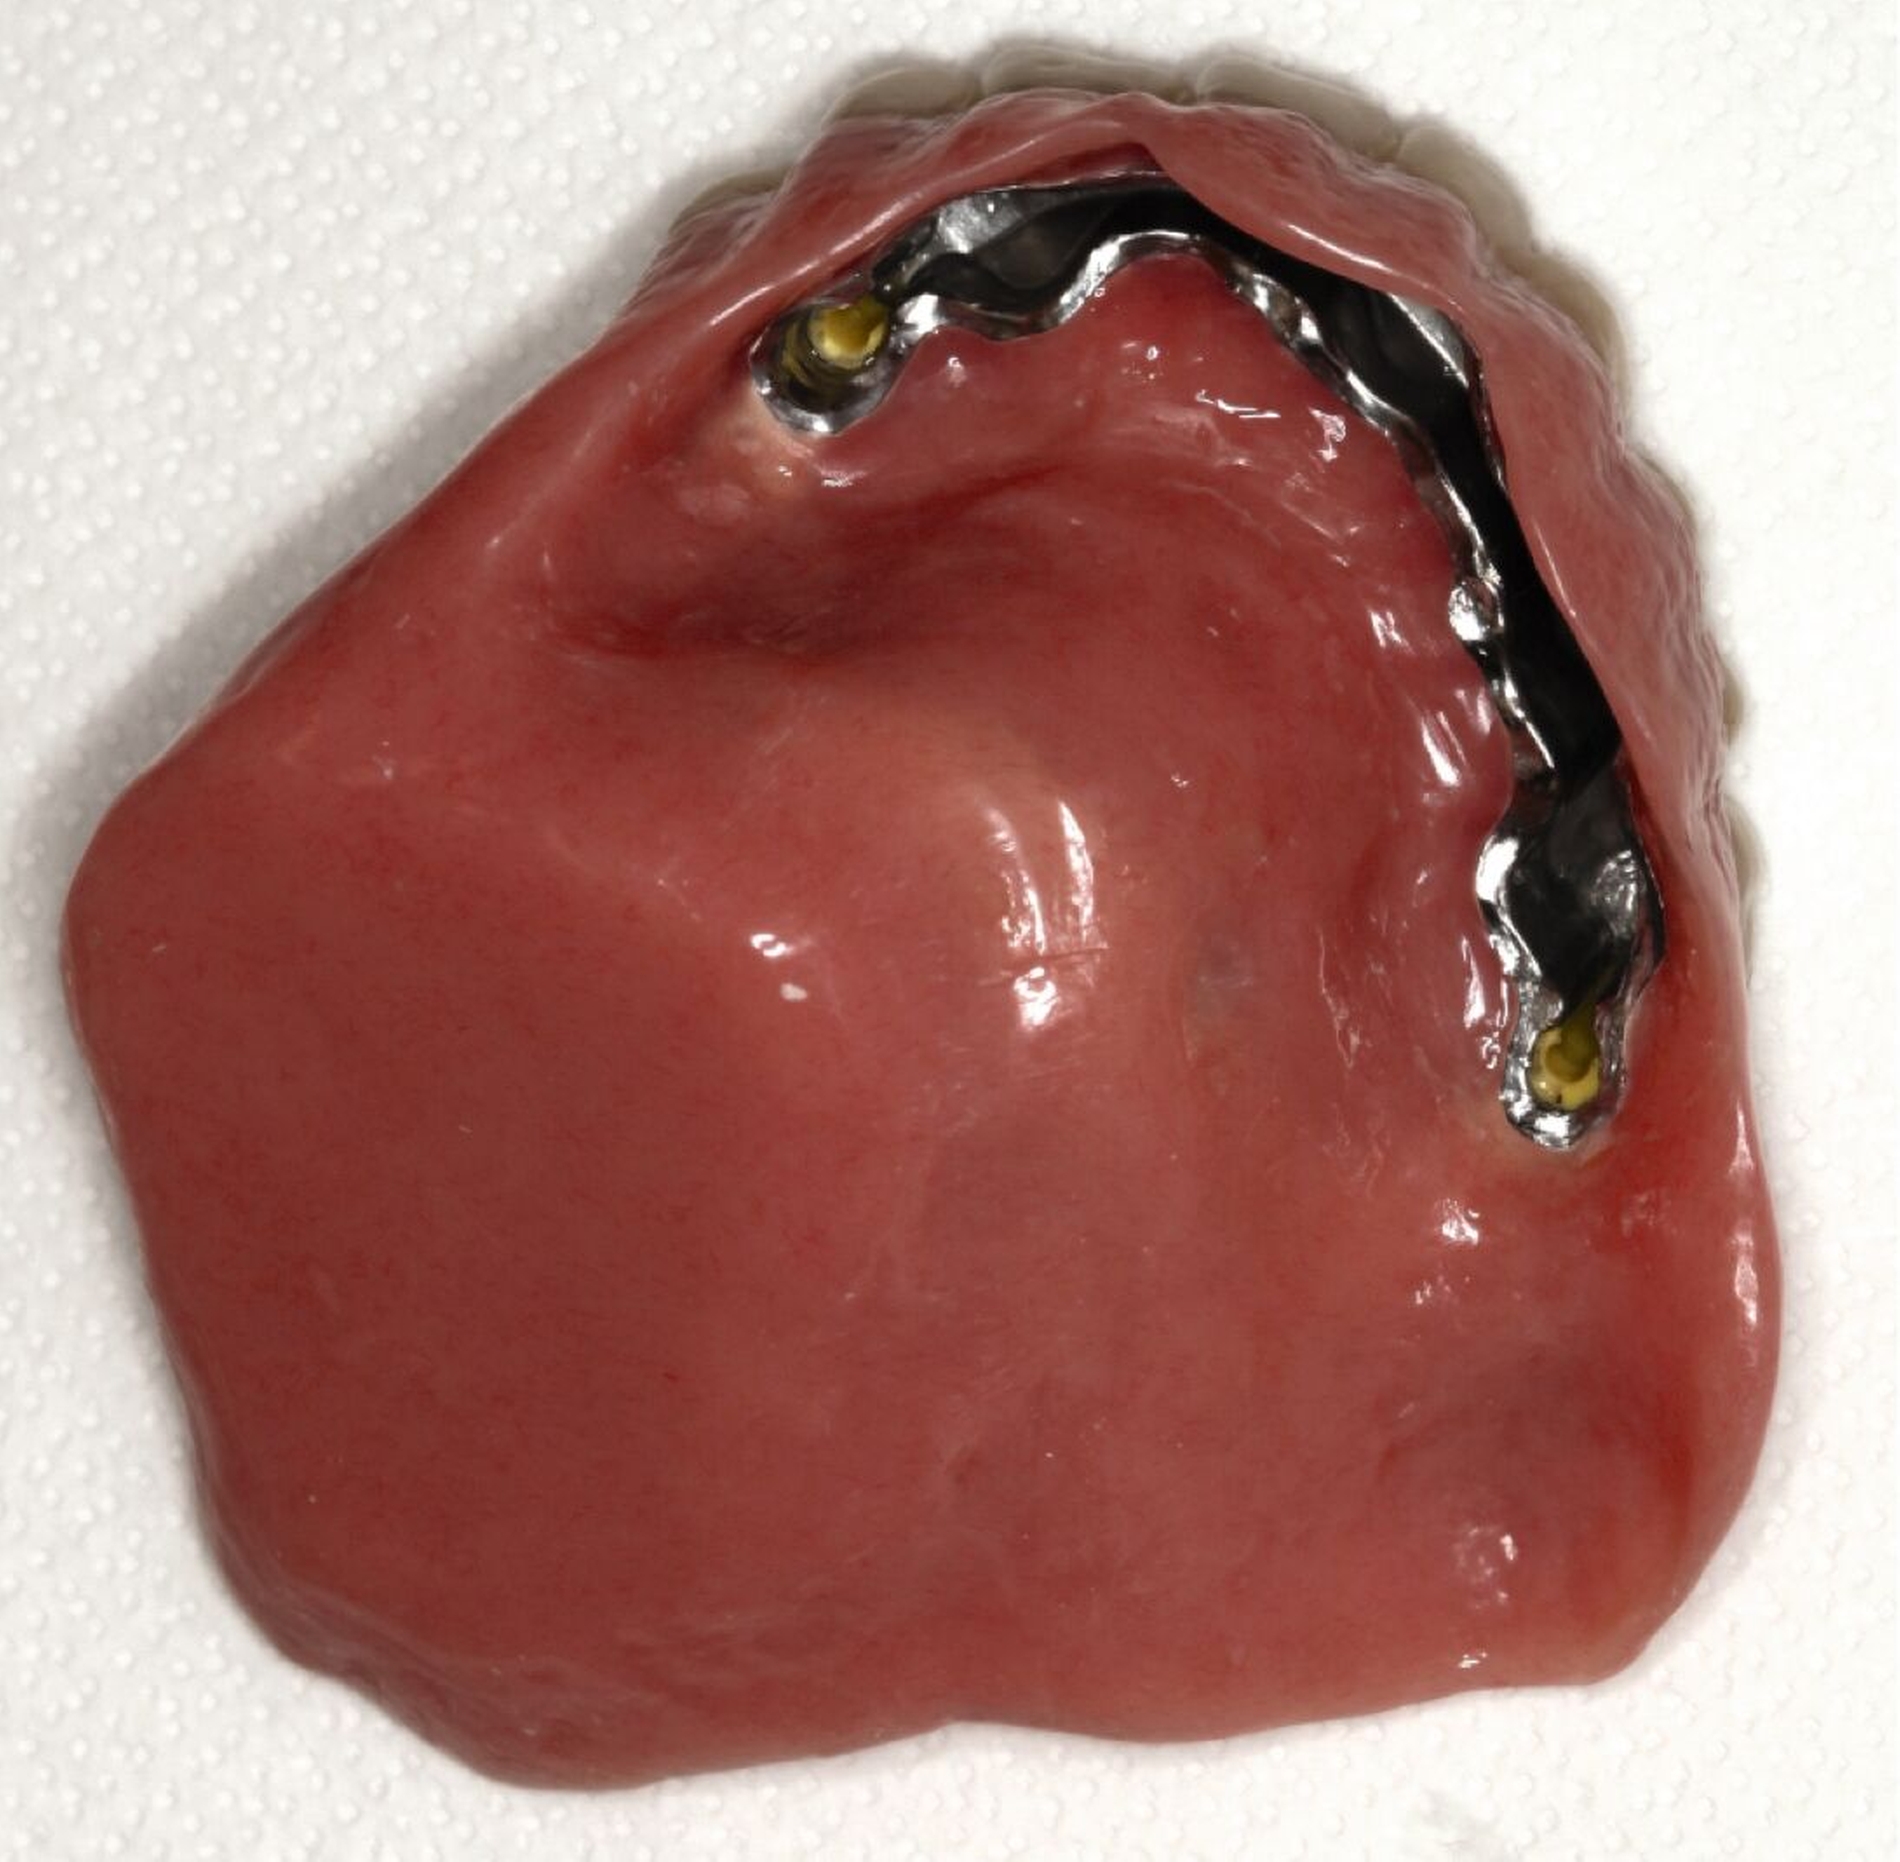

Silikon-Obturator

Ein Silikon-Obturator (Abbildung 1) wird über „unter-sich-gehende“ Bereiche im Defekt verankert, kann hohl oder massiv gestaltet sein und sollte im Mund über einen fein auslaufenden Rand (Federrand) am restlichen Weichgewebe enden. Durch diesen feinen Rand ist die Abdichtung zur Nase wie mit einem Saugstopfen sehr gut. Bei fehlendem Vestibulum ist ein fein auslaufender Rand technisch nicht möglich, weshalb durch einen Silikon-Obturator hier nur in seltenen Fällen ein zufriedenstellender Halt erreicht wird. Optimalerweise sollte der Silikon-Obturator täglich vom Patienten entfernt und gereinigt werden können, um die Ansiedlung von Pilzen zu vermeiden.

Ein Nachteil des Silikon-Obturators ist, dass das Ein- und Ausgliedern manuelles Geschick erfordert, was bei älteren Patienten nicht immer gegeben ist. Ebenso kann bei Veränderungen am Defekt, zum Beispiel durch Abheilen, kein Material angetragen werden, so dass meist ein neuer Obturator benötigt wird. In der Übergangsphase bis zur Fertigstellung des neuen Obturators steht der alte dem Patienten aber selbstverständlich als Verschluss zur Verfügung. Nach Einsetzen des neuen Obturators muss im Anschluss oft auch der Zahnersatz angepasst werden (Unterfütterung im Übergangsbereich Obturator–Prothese), was einen zusätzlichen Behandlungsschritt bedeutet.